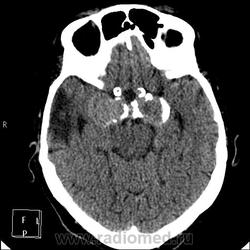

Да простят моё нахальство уважаемые специалисты КТ. Я вижу тут огромные инкапсулированные узлы расположенные почти симметрично справа и слева от турецкого седла, которое разрушено узлом поменьше. Латеральные злы продавливают дно средней черепной ямы. По-видимому, здесь доброкачественная опухоль типа «аденома», исходящая из гипофиза и давно растущая. Обызвествление есть не только в капсулах узлов, но и в их толще (очаговое). При таких размерах узлов и косных разрушениях, нет сомнения, пострадали и зрительные нервы.

Цифровых и плёночных доказательств на руках нет. Опухоль диагностирована в 2004 году, размером "с вишню", дебютировала птозом века правого глаза, умеренной головной болью в лобной области слева и постепенным снижением зрения, катаракта. Пациентка с трезвом уме и превосходной памяти (на мой субъективный взгляд))). В выписке результаты КТ, МРТ: неоперабельная опухоль селлярно-параселлярной области с прорастанием кавернозных синусов, аневризма сифона внутренних сонных артерий. Цитологию НЕ брали.

По поводу изменений правой височной области: и дочь, и сама пациентка отрицают в анамнезе инсульт.

Да, опухоль, в толще которой аневризма сифона ВСА. Причем с обеих сторон.

И то, и другое. Доказать без контрастирования не могу. Когда сама впервые увидела, анамнеза не знала, подумала о двусторонней аневризме. И не угадала.

Насчет опухоли у меня большие сомнения. То что седло растянуто, еще не показатель. Седло увеличивается в размерах даже при гипертонии,а тут такие аневризмы. Самой опухоли не видно, в просвете турецкого седла медиальные полюса аневризм. Ну впрочем не так это важно, интерес чисто теоретический, да и верификации видимо не будет. Спасибо большое за демонстрацию.

Случай-таки не верифицированный. Сочетание опухоли с аневрзмами - это очень странно. Боюсь, тут какая-то путаница.